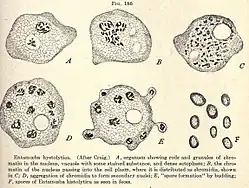

Morphologie

Le genre Entamoeba se caractérise par un noyau ayant l'aspect d'un anneau après coloration, avec une chromatine disposée en petit amas central (dit caryosome) et en couche périphérique.

Entamoeba histolytica peut se présenter sous deux aspects différents : le trophozoïte, forme cellulaire végétative mobile et de multiplication, et le kyste, forme immobile, de résistance et de contamination[11].

Le trophozoïte présente à son tour deux formes :

- Entamoeba histolytica minuta, de petite taille (en latin : minuta signifie « petit »), soit 10 à 15 µm. C'est une forme infestante qui se comporte en saprophyte restant à l'intérieur du colon, et qui ne donne aucun symptôme (sujet «porteur sain»).

- Entamoeba histolytica histolytica, plus volumineuse, de 20 à 30 ou jusqu'à 40 µm. C'est une forme invasive, véritablement parasitaire, hématophage, qui envahit la muqueuse colique et peut migrer vers d'autres organes, en étant responsable de l'amœbose maladie.

Entamoeba histolytica histolytica présente le même aspect général que minuta, avec des caractères supplémentaires, comme la présence d'hématies en voie de digestion dans des vacuoles cytoplasmiques (d’où le nom d’histolytica)[11].

Le kyste (10 à 16 μm) est sphérique, entouré d'une enveloppe résistante. Initialement, un kyste immature contient une vacuole stockant du glycogène, des agrégats de ribosomes, et un noyau. Par division du noyau, le kyste mûrit en deux puis quatre noyaux pour devenir un kyste à pouvoir infectieux[17]. Il survit au minimum 10 jours à 18 °C, ou 3 mois à 4 °C, dans le milieu extérieur[18]. C'est la forme de dissémination, qui résiste bien aux agents chimiques.